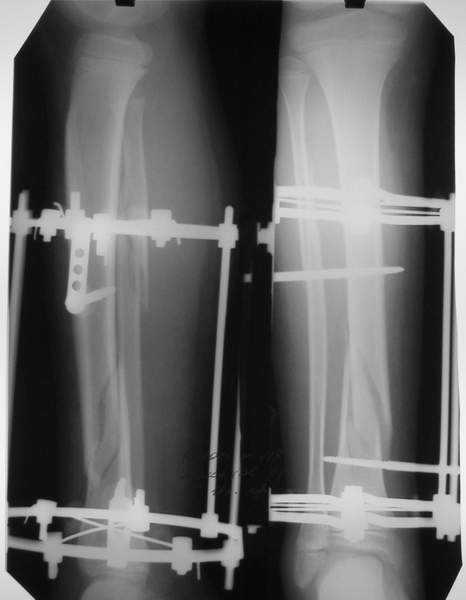

В аттачтах №№ 1 и 2 - примеры, когда 2 кольца не позволили послеоперационно

исправить смещение фрагментов большеберцовой (по ширине и вальгусное).

А казалось бы (#2) - поиграй на штангах и все влетит.

Оперировал не я

:-)

2

3a